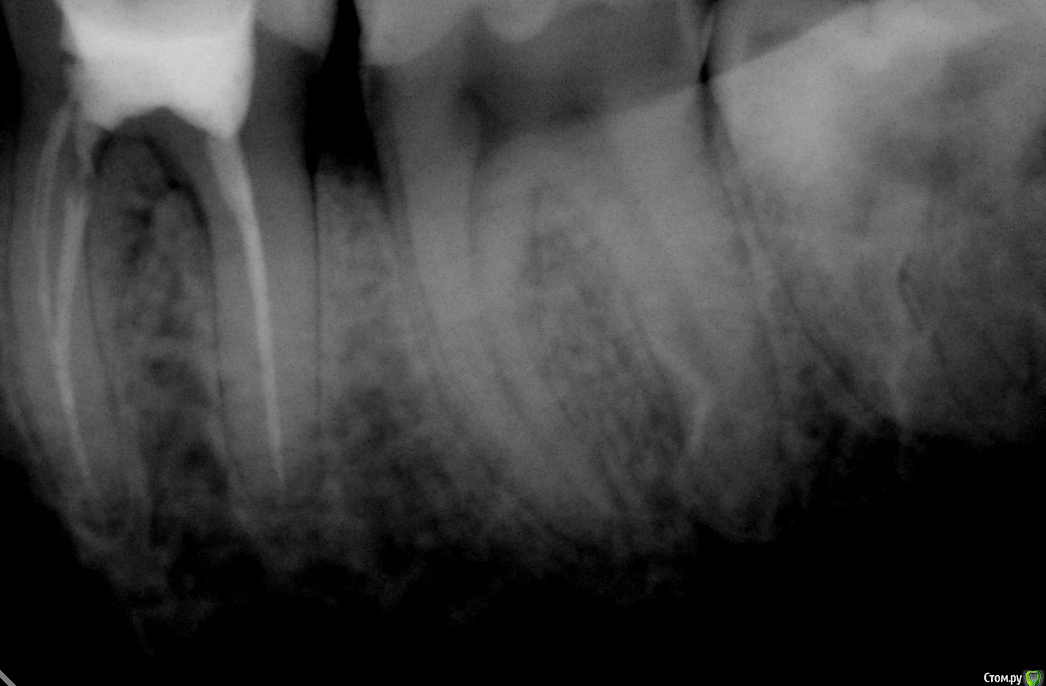

Jea Опубликовано 24 декабря, 2015 Поделиться Опубликовано 24 декабря, 2015 Добрый день! Помогите разобраться в сложившейся ситуации. Очень нужна оценка проведенного лечения сторонним экспертом. Хронология событий: 07.11 - первичный прием. Жалобы: ноющая боль в 7м левом нижнем зубе, носящая периодический характер, усиливающаяся в ночное время. Реакции на горячее/холодное, кислое/сладкое не было. Установленный диагноз: пульпит. Проведенные манипуляции: удаление нервов. 14.11- Пломбировка каналов. 21.11 - установка постоянной пломбы. 20.12 - повторное обращение по проведенному раннее лечению. Жалобы: боль после лечения не проходящая в течении месяца (нояющая, усиливающаяся в ночное время, при надкусывании). Есть левой стороной я не могла. Диагноз: воспалительный процесс в зубе. Манипуляции: распломбировка каналов, закладка лекарства, временная пломба. В течение 2х дней сильные постпломбировочные боли. Вечером 22.12 опухла десна. 23.12 прием по осложнениям после лечения, в ходе которого выяснилось, что во время распломбировки каналов зуб треснул и внесенное в канал лекарство вылилось в десну. Предложенный план лечения: удаление+ имплантация. Необходима оценка качества проведенного лечения и прогноз на дальнейшее лечение зуба. Прикрепляю все снимки, сделанные в ходе лечения. Благодарю! Ссылка на комментарий

red_butler Опубликовано 25 декабря, 2015 Поделиться Опубликовано 25 декабря, 2015 Как скоро мне необходимо удалить зуб? если в настоящее время зуб не беспокоит, то отложите решение на после праздников. В Вашем случае возможна одномоментная имплантация. А также по поводу соседней 6ки. Надо ли перелечивать каналы? Если да, то что ставить: пломбу или коронку? как минимум нужна ревизия корневых каналов и в дальнейшем коронка. 1 Ссылка на комментарий